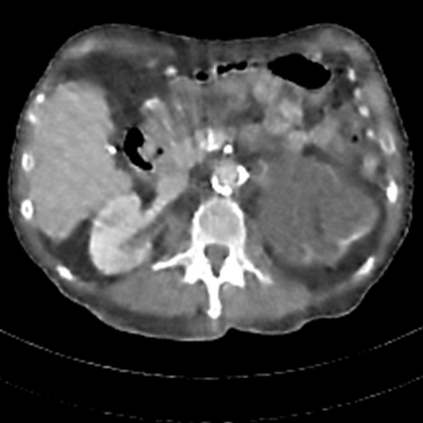

Sparse-view computed tomography (CT) -- using a small number of projections for tomographic reconstruction -- enables much lower radiation dose to patients and accelerated data acquisition. The reconstructed images, however, suffer from strong artifacts, greatly limiting their diagnostic value. Current trends for sparse-view CT turn to the raw data for better information recovery. The resultant dual-domain methods, nonetheless, suffer from secondary artifacts, especially in ultra-sparse view scenarios, and their generalization to other scanners/protocols is greatly limited. A crucial question arises: have the image post-processing methods reached the limit? Our answer is not yet. In this paper, we stick to image post-processing methods due to great flexibility and propose global representation (GloRe) distillation framework for sparse-view CT, termed GloReDi. First, we propose to learn GloRe with Fourier convolution, so each element in GloRe has an image-wide receptive field. Second, unlike methods that only use the full-view images for supervision, we propose to distill GloRe from intermediate-view reconstructed images that are readily available but not explored in previous literature. The success of GloRe distillation is attributed to two key components: representation directional distillation to align the GloRe directions, and band-pass-specific contrastive distillation to gain clinically important details. Extensive experiments demonstrate the superiority of the proposed GloReDi over the state-of-the-art methods, including dual-domain ones. The source code is available at https://github.com/longzilicart/GloReDi.